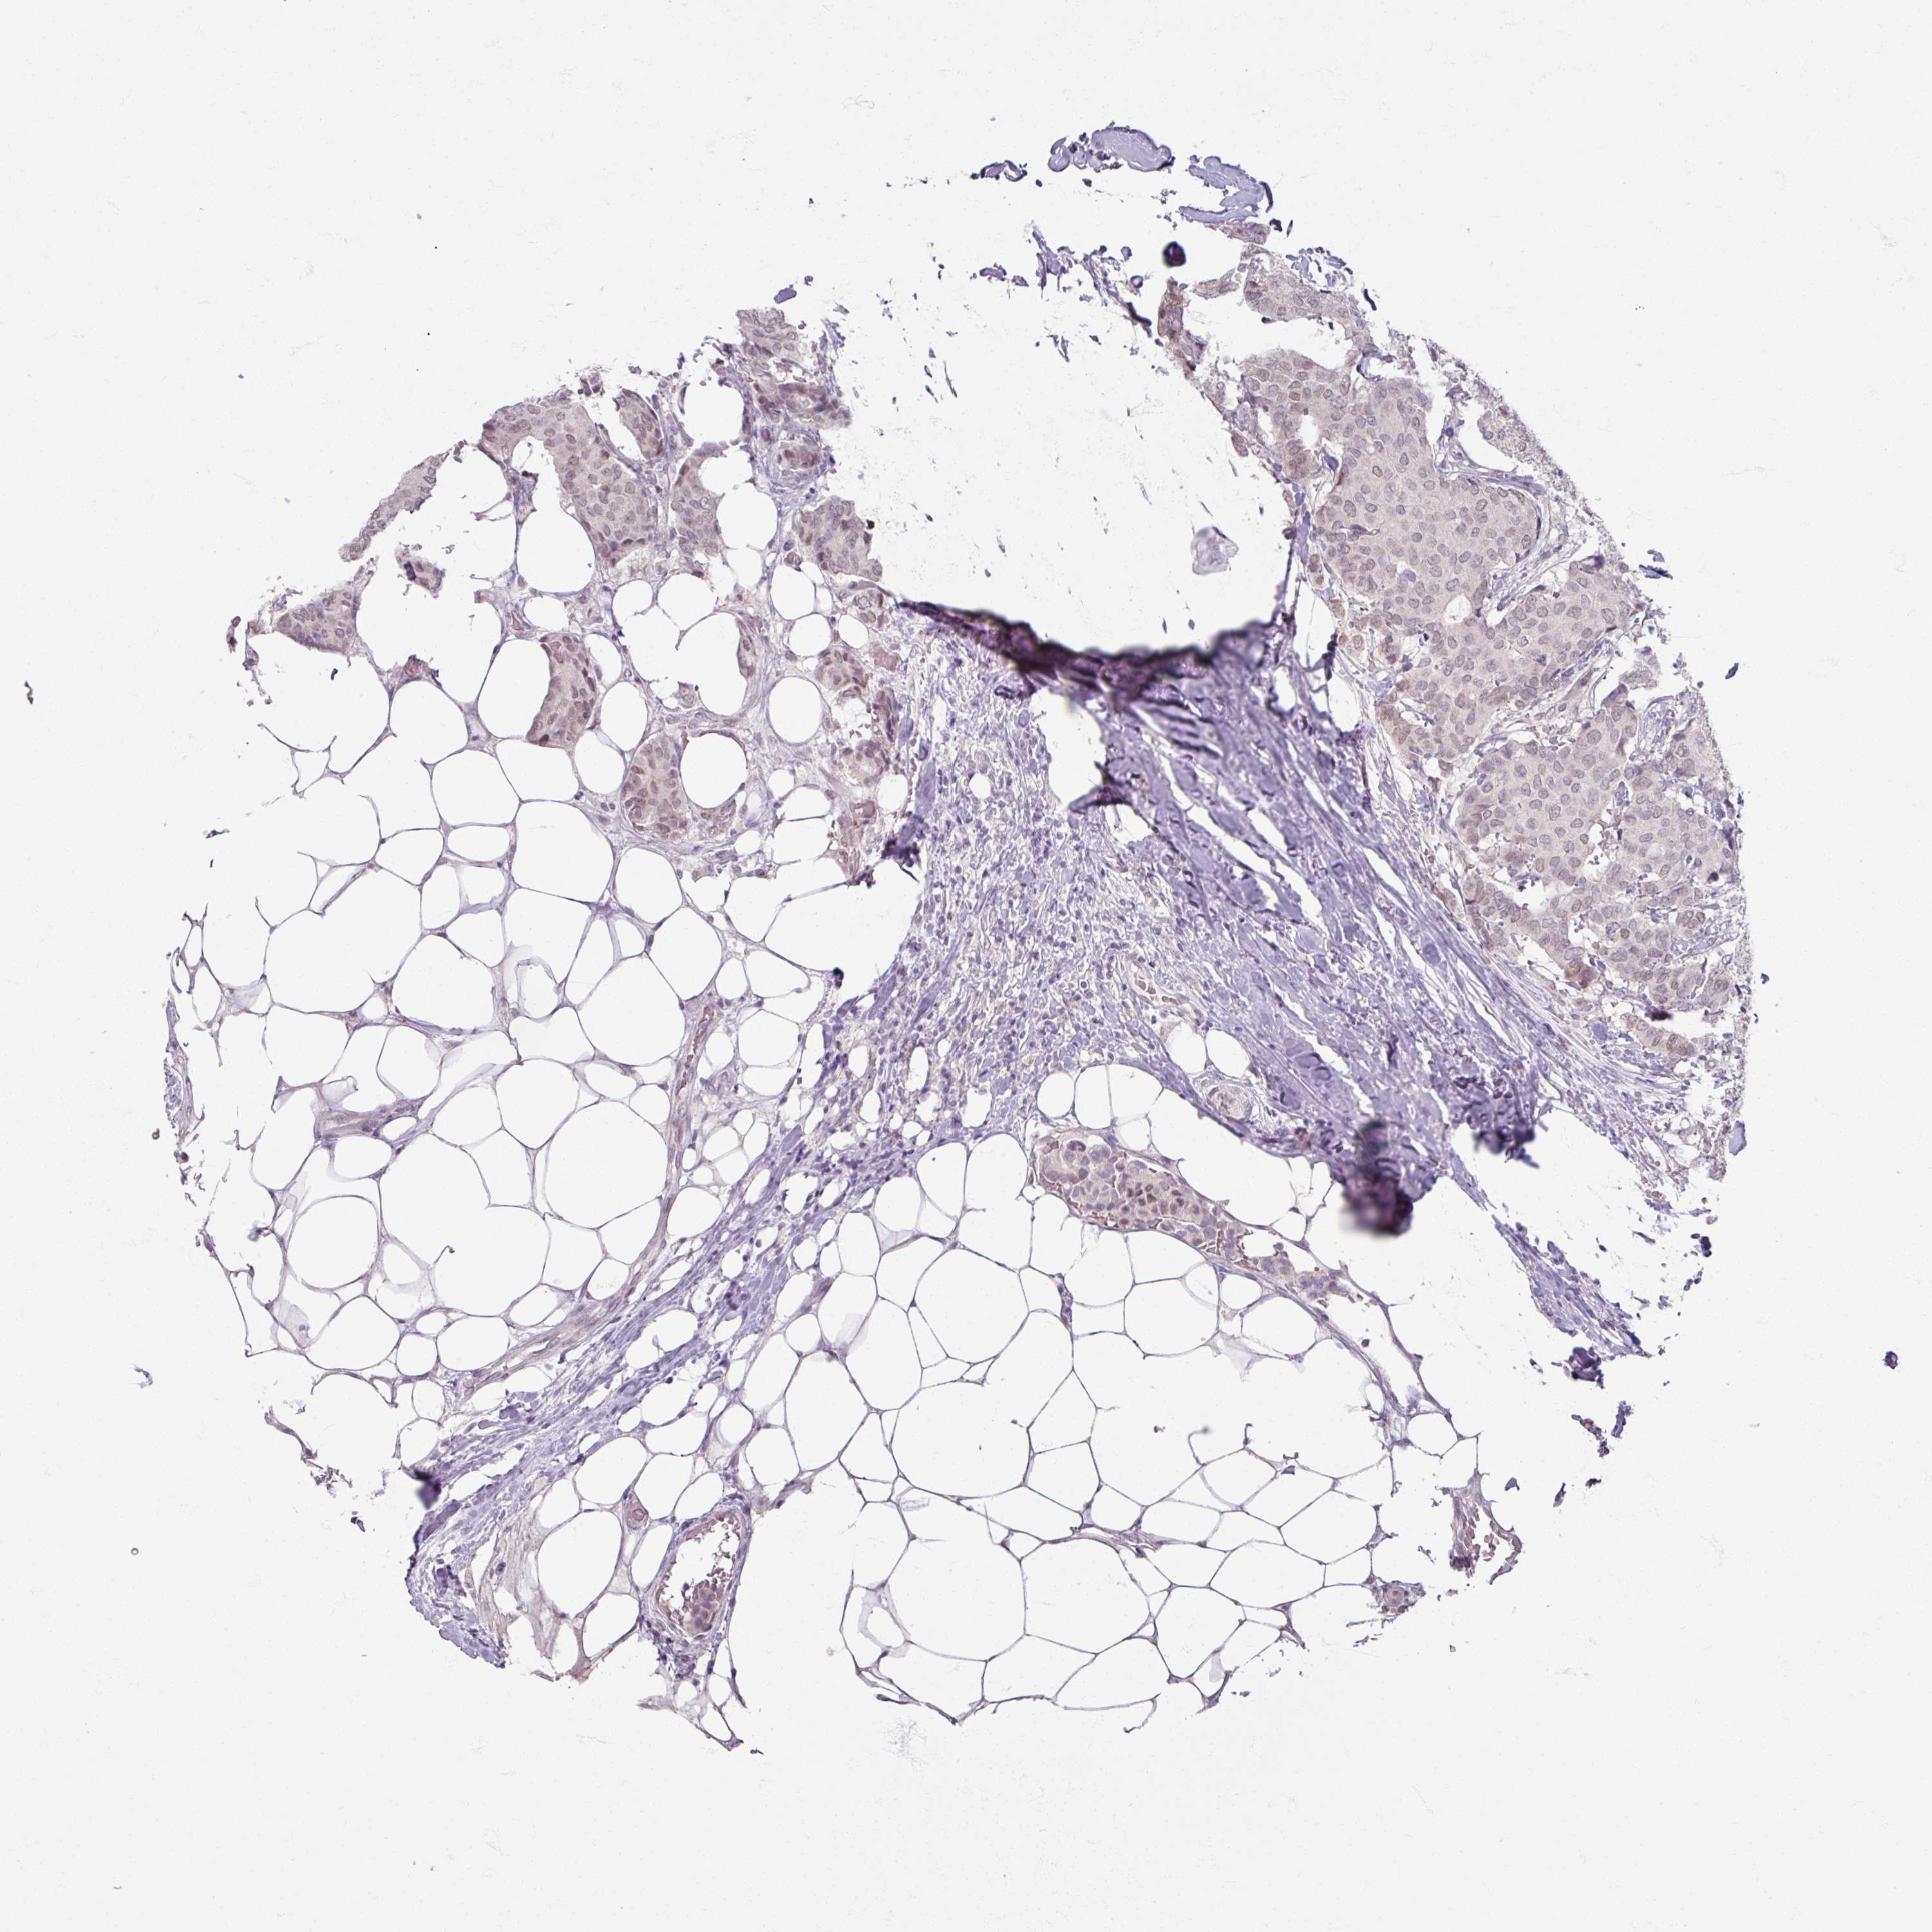

CANCER BREAST CANCER Show tissue menu

BRCA TCGA BRCA VALIDATION PROTEIN EXPRESSION

ANTIBODIES

AND

VALIDATION